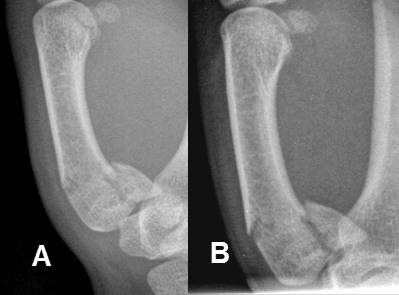

Fig 199. Fractura de Monteggia.

A: Rx AP y B: Rx lateral. Fractura conminuta con angulación anterior del cúbito proximal (Flecha delgada) y luxación en la cabeza del radio. (Flecha gruesa).